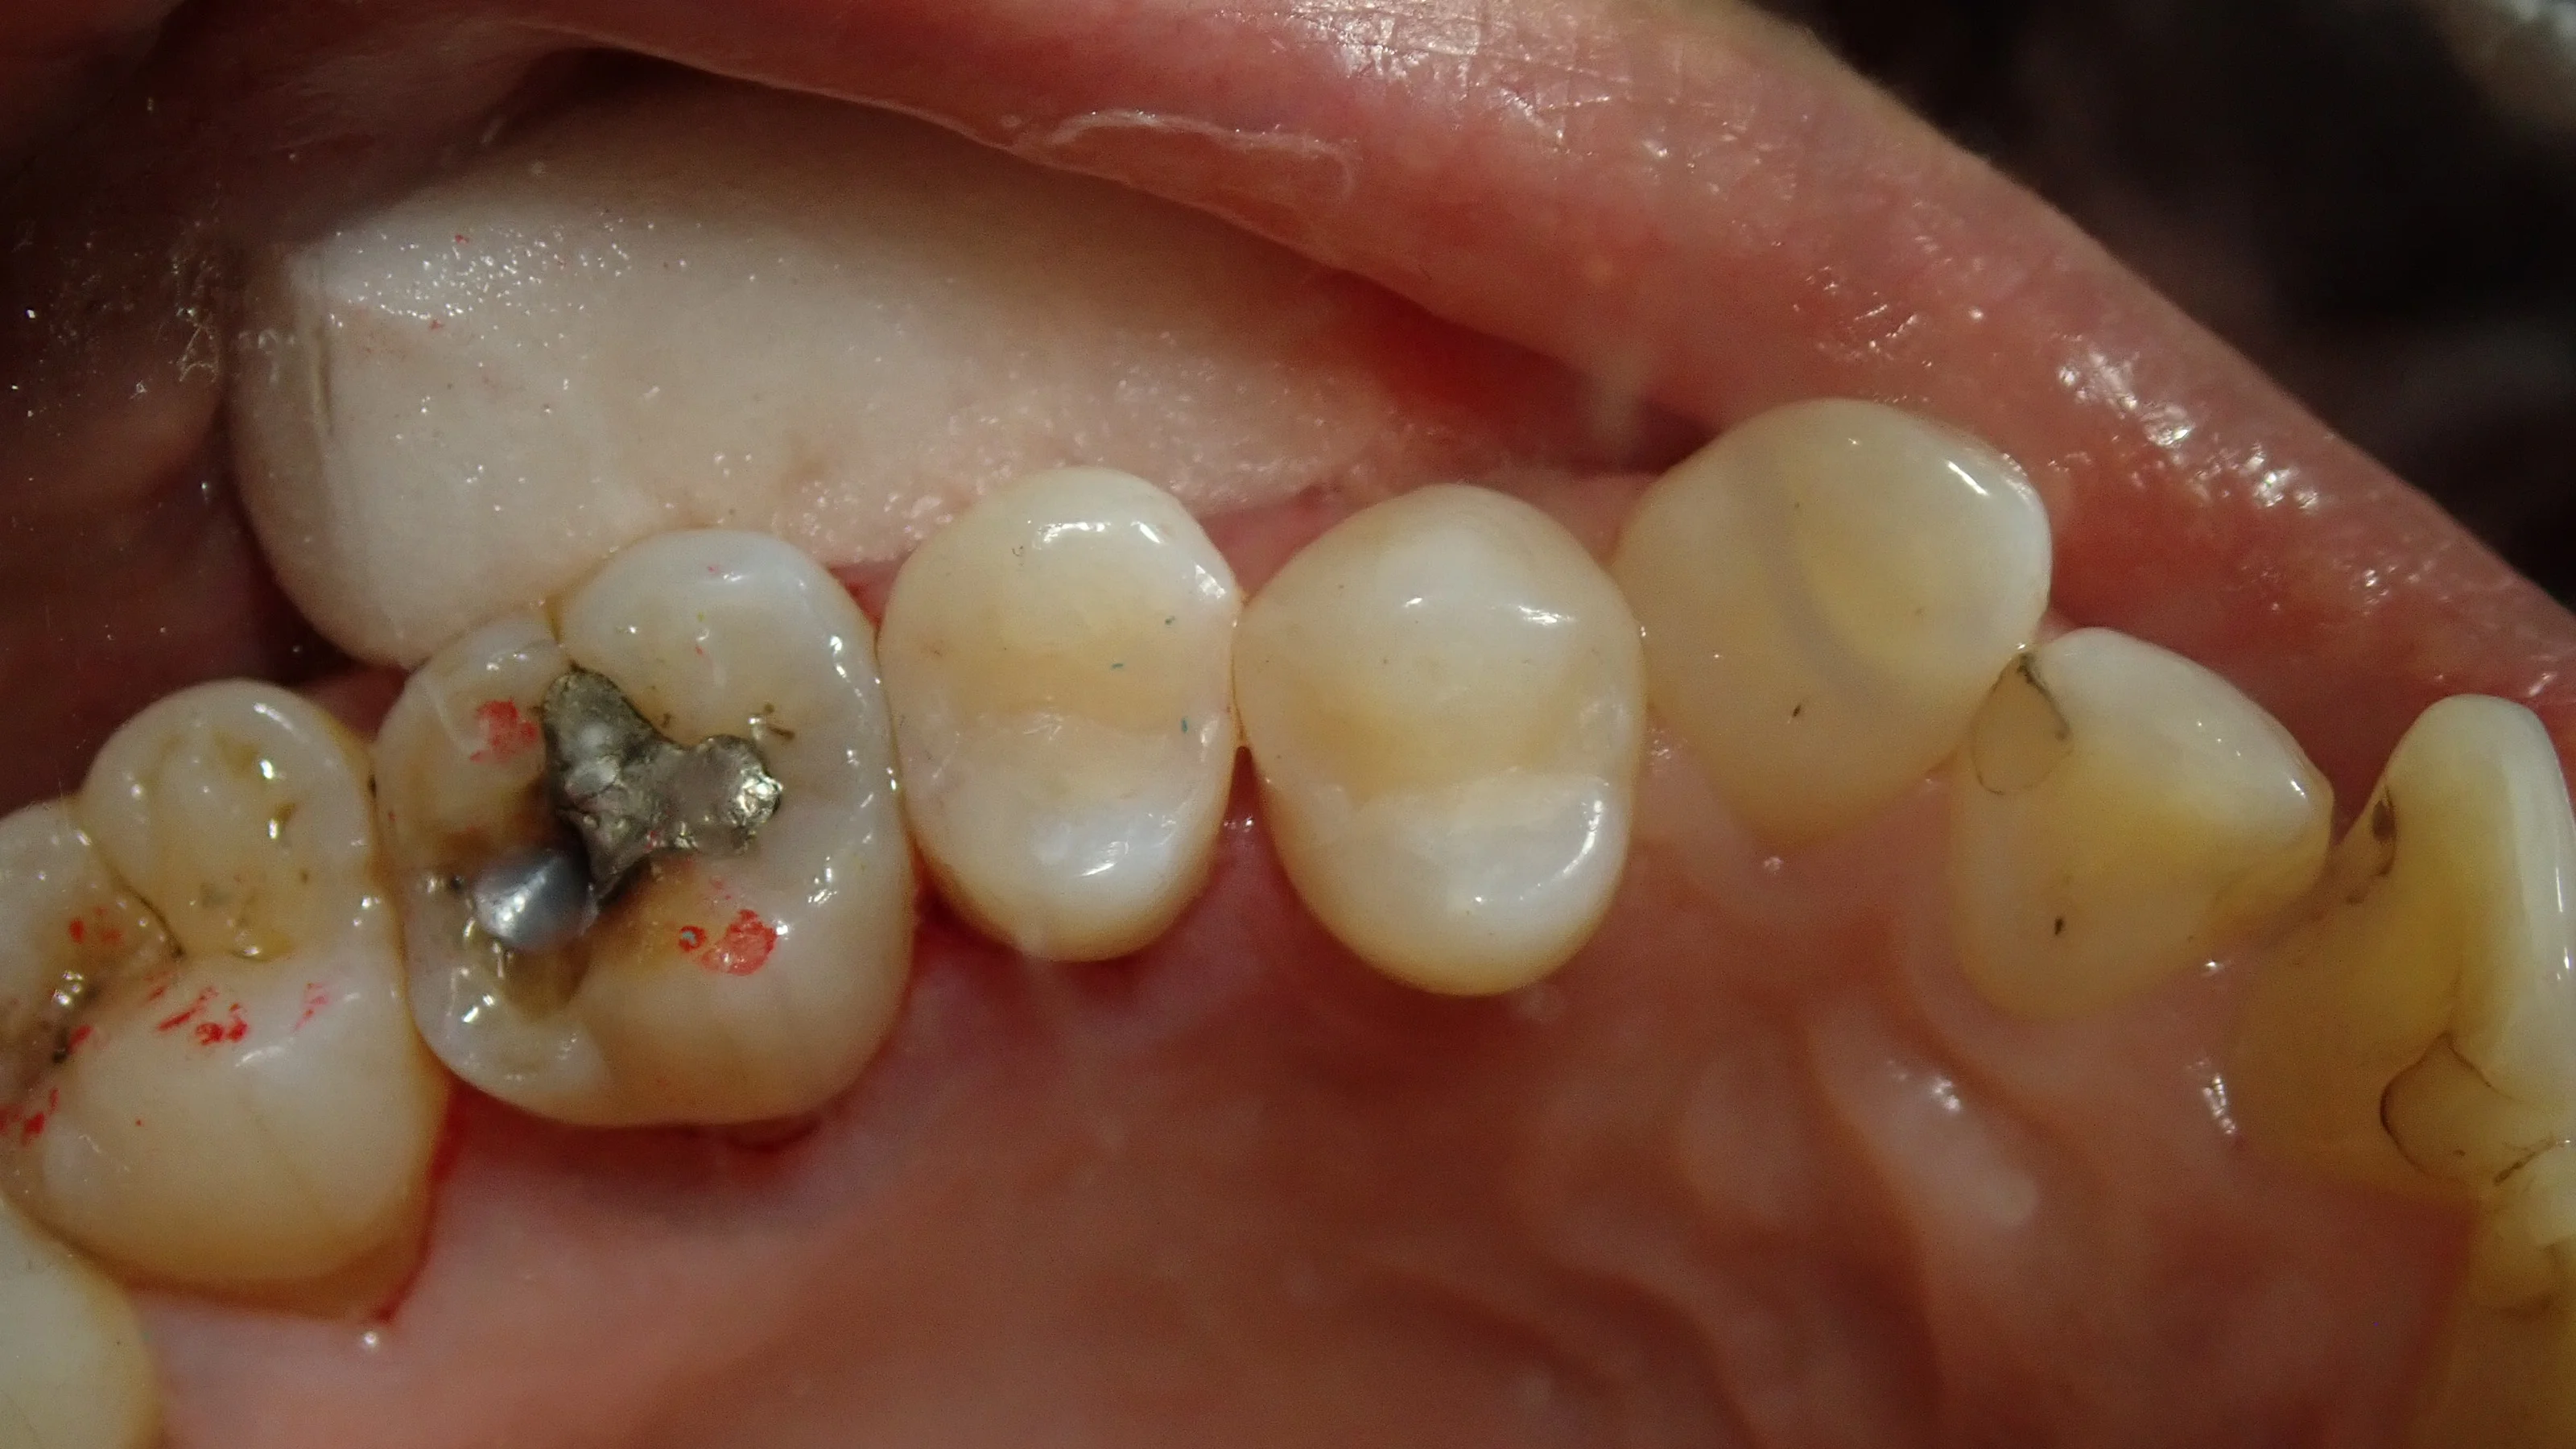

十分な止血後に、詰め物を詰めたのがこちらです。

歯との間に段差などは付かずに綺麗に詰められたかと思います。

術前術後の比較がこちらです。

基本的に保険診療では審美的な治療を行う事はご法度となっていますし、その治療単価も非常に低く設定されています・・・。

そのため、ステインなどは入れられませんし、時間をかけて本来の歯の形に近い造形をすることもできませんので、ダイレクトボンディングに比べるとどうしてもこういったのっぺりとした印象のする詰め物になってしまいます。

それでも、治療後の写真をお見せしたら患者さんには非常に喜んでいただけました。

フロスなどのひっかかりはもちろんない様に仕上げていますので、歯間ブラシ・フロスの活用を頑張って頂ければそこそこ持たせることは出来るかと思います。